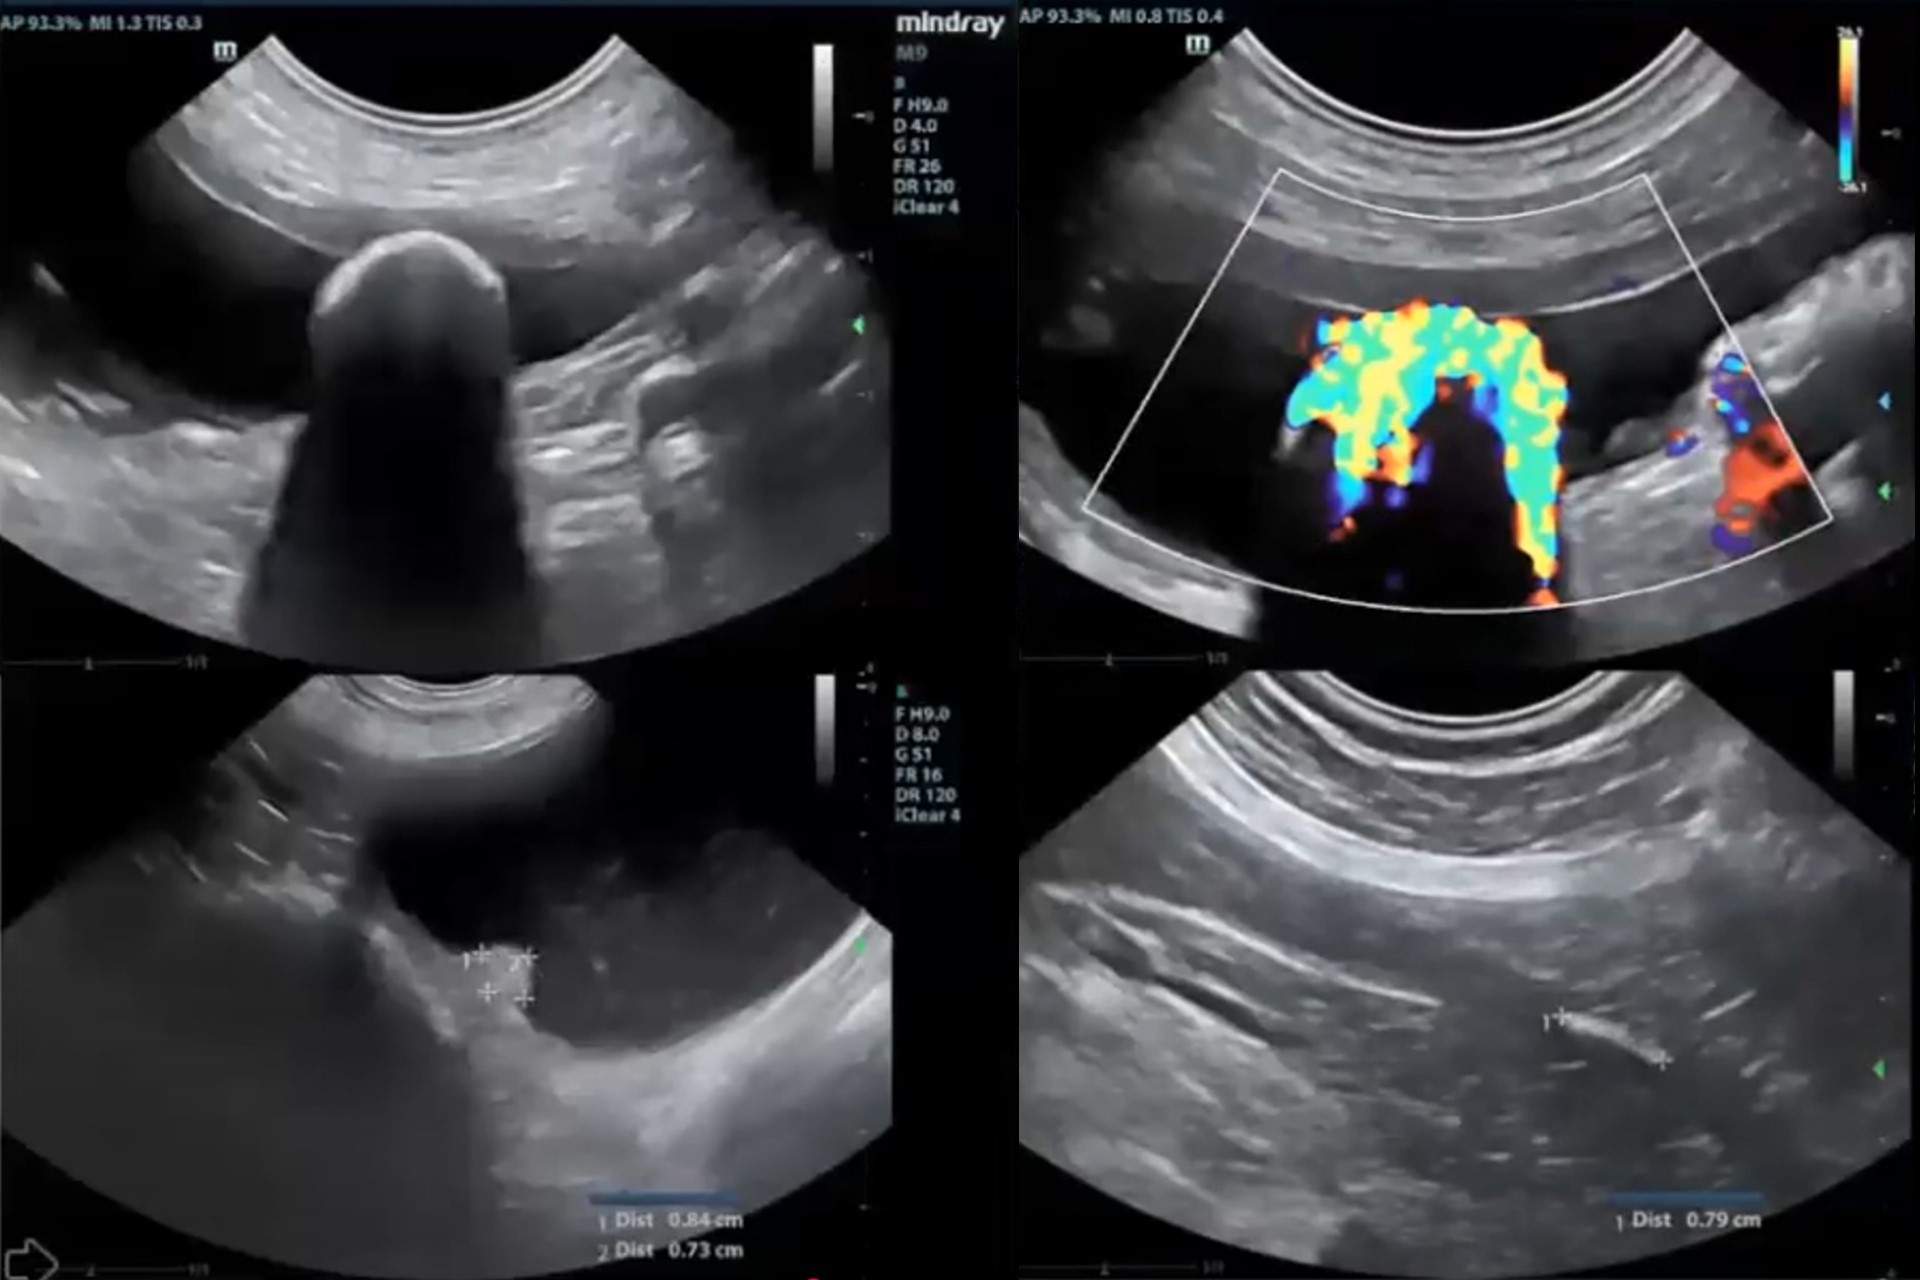

Ecografía Doppler

Evaluación de los grandes vasos, la vasculatura renal y hepática. Permite diagnosticar patologías vasculares, alteraciones del flujo sanguíneo y monitorizar enfermedades cardiacas o sistémicas.